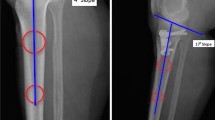

Several theories exist regarding the etiology of PTS change following HTO. One widely discussed theory is that the triangular shape of the proximal tibia is responsible for the PTS increase. The bone’s shape demands as a matter of geometry a smaller opening of the osteotomy anteriorly (which is closer to the osteotomy hinge) than posteriorly if the PTS is to remain unchanged [2, 11, 17]. Anterior plate placement may compound this problem by more effectively opening the osteotomy anteriorly [17–20]. Another factor affecting the PTS is the location of the cortical hinge on the lateral side. If the osteotomy is not performed in the frontal but rather in an oblique plane with the hinge posterolateral, the PTS can be increased [21]. According to Marti, an incomplete posterior osteotomy cut and inappropriate release of posterior soft tissues can be responsible for a PTS increase, resulting in increased opening anteriority [9]. In addition to the PTS change, tibial rotation can also be modified during opening wedge HTO; however, very little evidence about this subject is available in literature [22, 23]. Change of rotation cannot be reliably evaluated on standard radiographs, and clinical examination is not sensitive for small changes up to 5°.

Intra-operative PTS and tibial rotation control can be measured by different methods including computer navigation [23–26] and control with two parallel K-wires proximal and distal of the osteotomy [27]. Moreover, the PTS change can be estimated intra-operatively by judging the anterior osteotomy gap to be one half to two thirds of the posterior gap [11, 25] and by ensuring that there is no change in the degree of extension possible before osteotomy and after fixation [25].

To mimic a realistic intra-operative setting, the cadavers were placed in supine position. A longitudinal anteromedial incision was made and utilized to create a medial arthrotomy and a standard anteromedial approach to the proximal tibia. The arthrotomy was required for referencing for the navigation system and allowed assessment of the degree of degenerative change present in the knee joint. The arthrotomy was closed with sutures after referencing. The distal part of the incision was then continued below the pes anserinus insertion, and the pes tendons, patellar tendon insertion, and medial collateral ligament (MCL) were identified. The osteotomy site was marked just proximal to the pes anserinus and included sectioning of the superficial MCL just above the upper pes anserinus margin. The descending insertion of the semimembranosus and the proximal part of the superficial MCL insertion remained intact. An ACL guide was then used to place a K-wire from the medial starting point laterally to the desired location of the hinge on the lateral tibia. This point was located 1–2 cm distal to the lateral joint line in all cases. To secure the lateral hinge during the measurements, an external fixator was placed laterally, bridging the lateral hinge location (Fig. 1). The reference markers for the computer navigation system were placed as detailed below.

The computer navigation system used included PLEOS® Knee software and the PLEOS® platform (TORNIER, Saint-Ismier, France). The system has previously validated precision to within 1° of rotation around 3 axes and 1 mm of translation along three axes [28]. Software modification was done specifically for this study to allow assessment of the motion of the proximal and distal segments of the tibia independently. Three trackers were fixed with two-threaded pins on the femur, proximal tibia, and distal tibia (Fig. 1). The setup allowed real-time measurement of the hip–knee–ankle angle and knee flexion angle. Software modification allowed measurement of motion between the proximal and distal tibia trackers, including the osteotomy opening angle (rotation around the z-axis), PTS change (rotation around the x-axis), and rotational change (rotation around the y-axis). Acquisitions were stored as screen capture and were later migrated to statistics software.

Surgery and measurement course